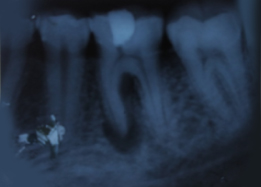

Immediate Post-Surgical IOPAR